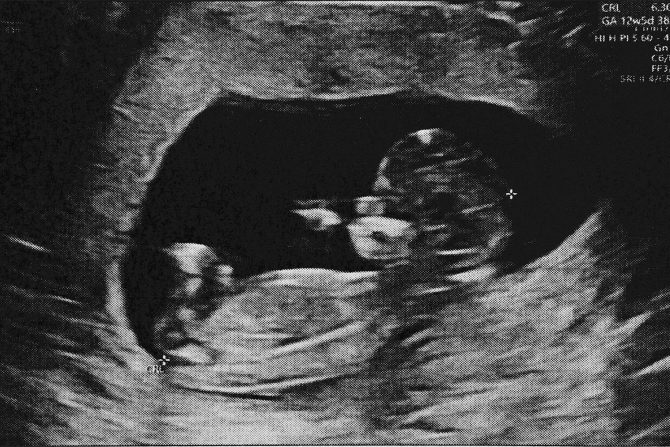

Placenta raste zajedno sa fetusom i do trenutka porođaja može da teži do 500 grama i da bude dugačka 23 centimetra

Posteljica ili placenta je organ koji se usađuje u zid materice i razvija u trudnoći sa zadatkom da obezbedi bebi hranjive sastojke i kiseonik. Placenta uklanja otpadne materije iz bebine krvi i iz nje se formira pupčana vrpca. Posteljica može da bude usađena na zadnji, prednji deo materice, sa boka ili pri vrhu materice i retko u donjem delu materice. Na osnovu položaja posteljice ginekolozi akušeri određuju da li će porođaj biti vaginalnim putem ili carski rez.

Posteljica može da se implantira na bilo koje mesto u zidu materice. Kada se pričvrsti za zadnji deo materice, zove se posteljica na zadnjem zidu materice.

Placenta raste zajedno sa fetusom i do trenutka porođaja može da teži do 500 grama i da bude dugačka 23 centimetra. Posle rađanja bebe, materica se naknadno kontrahuje kako bi se oslobodila posteljice.